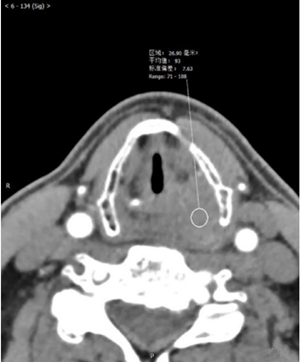

影像图片

评论: 声门上层面喉左后壁增厚,呈软组织密度肿块影,边界不清,左侧杓状软骨大部分显示不清,左侧甲状软骨边缘毛糙,增强扫描呈渐进性轻度强化。